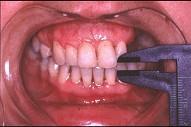

关于颞下颌关节强直(如图)的描述哪项是正确的 ( ) A.颞下颌关节外强直是关节外纤维黏连 B.颞下颌关节内强直是关节内骨性黏连 C.混...

问题 关于颞下颌关节强直(如图)的描述哪项是正确的 ( )

选项 A.颞下颌关节外强直是关节外纤维黏连 B.颞下颌关节内强直是关节内骨性黏连 C.混合性下关节强直是指关节内,外强直同时发生,又称颌间挛缩 D.关节及关节周围组织器质性病变造成开口困难或完全不能开口 E.颞下颌关节强直常常突然发生

答案 D